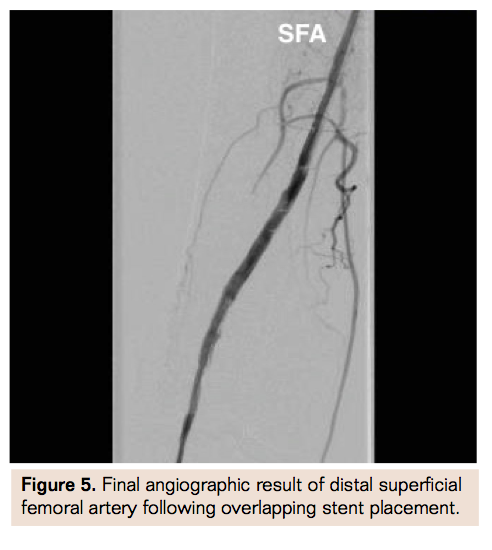

Due to the lack of contralateral CFA access secondary to prior bleed and covered stent placement, history of chronic thrombocytopenia, and increased risk of recurrent access bleed with antegrade access, the decision was made to obtain retrograde pedal access for revascularization. Using ultrasound guidance and a micropuncture access kit (Cook Medical), a 6 Fr sheath was placed in the right posterior tibial (PT) artery (Figure 1). Selective angiogram through the transpedal sheath confirmed distal popliteal occlusion extending into the PT with collateral filling of the anterior tibial artery (Figure 2). The popliteal occlusion was crossed using a glidewire and support catheter into the proximal SFA. Selective angiogram from this segment confirmed occlusion of the SFA at the distal edge of the previous stent (Figure 3). Rheolytic thrombectomy (Medrad Interventional) was performed through the occluded segment followed by balloon angioplasty with improvement in flow and small residual distal stent edge dissection (Figure 4). A Supera self-expanding stent (Abbott Vascular) was placed in overlapping fashion at the distal SFA stent edge with excellent angiographic result (Figure 5) and brisk runoff into the PT (Figure 6). Hemostasis was achieved in the posterior tibial artery access site using a RadAR compression device (Advanced Vascular Dynamics) (Figure 7). The patient was discharged home the following day with dual antiplatelet therapy regimen for an indefinite duration.